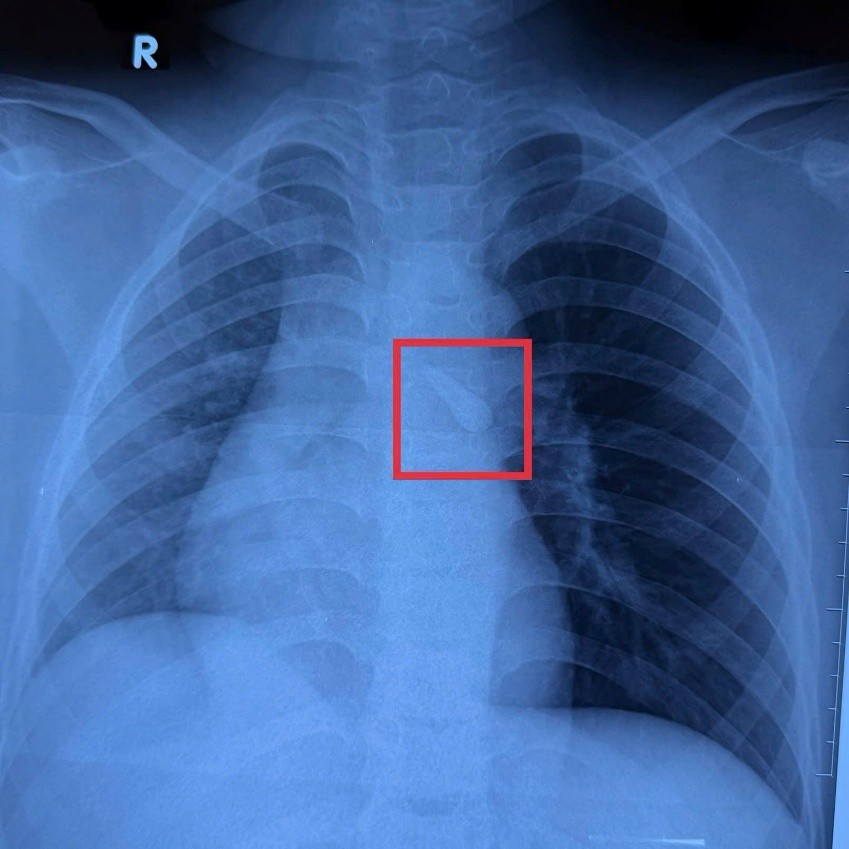

Hình ảnh X-quang của bé ghi nhận một dị vật cản quang ở khí quản. Khai thác bệnh sử và tổn thương vùng hàm mặt thấy bé bị mất răng số 21, từ đó nghĩ đến khả năng răng bị hít sặc vào đường thở sau chấn thương mà bé không để ý.

Hình ảnh X-quang của bé ghi nhận một dị vật cản quang ở khí quản - Ảnh BVCC

Bé được chẩn đoán: Vỡ xương sàn ổ mắt; Đụng giập nhãn cầu; Dị vật đường thở (răng); Chấn thương đầu; Vết thương đầu sau tai nạn giao thông. Bệnh nhi nhanh chóng được hội chẩn liên chuyên khoa Ngoại thần kinh- Ngoại tổng hợp- Mắt- Răng hàm mặt-Tai mũi họng.

Trước nguy cơ tắc nghẽn đường thở và các biến chứng hô hấp nguy hiểm, bệnh nhi được ê-kíp bác sĩ chỉ định nội soi đường thở can thiệp khẩn, cũng như ổn định các tình trạng chuyên khoa khác. Ca phẫu thuật được thực hiện bởi TS.BS Phú Quốc Việt, Phó khoa Tai mũi họng Bệnh viện Nhi đồng 1, với sự phối hợp chặt chẽ của ê-kíp gây mê – hồi sức.

Qua nội soi, TS.BS Việt ghi nhận dị vật là một chiếc răng nằm trong carina của khí quản và đã gắp ra thành công. Sau phẫu thuật, đường thở của bệnh nhi thông thoáng, không ghi nhận chảy máu hay biến chứng. Trẻ tỉnh táo, hô hấp ổn định, ăn uống được và tiếp tục được theo dõi tại khoa.